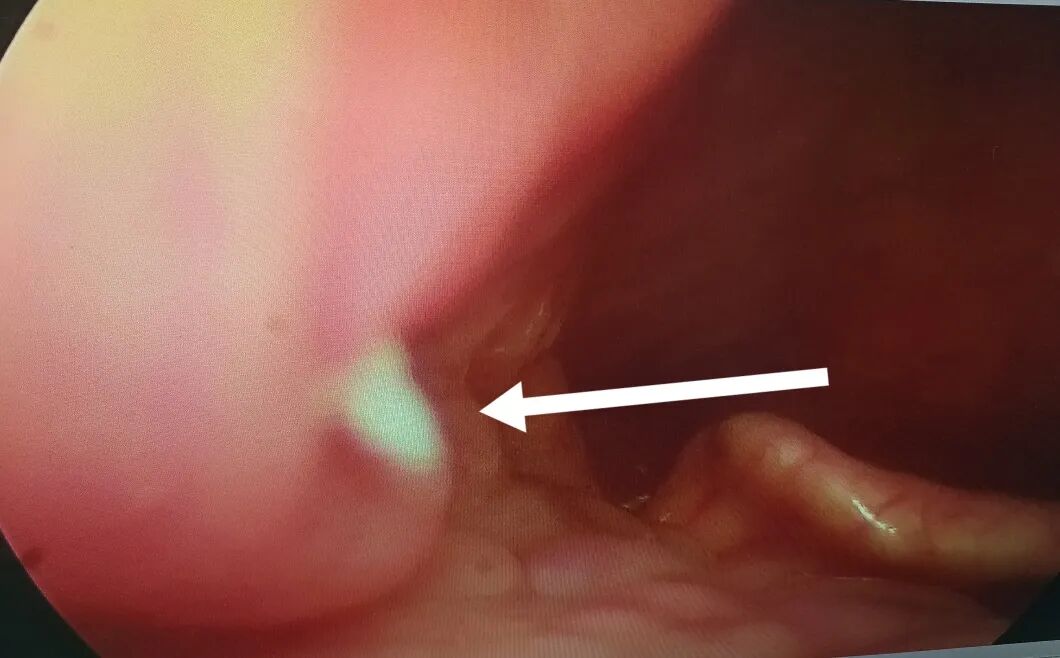

科主任曹永华接诊后,在喉镜的帮助下,在患者咽喉部深处找到了一根清晰的白色鱼刺,使用鱼刺钳将鱼刺完整取出。

喉镜下的鱼刺

鱼刺被取出的那一刻,周女士舒了一口气顿感轻松,急忙向医生道谢。听说她喝醋、吃馒头这些不靠谱的“土方法”,曹永华赶紧给大家科普科普——